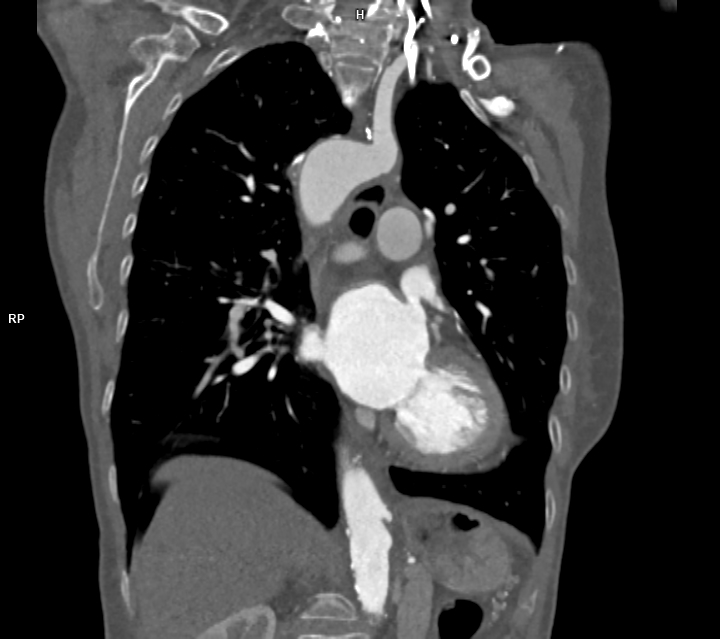

CAZ nr 57: Arc aortic de partea dreaptă si diverticul Kommerell

Figura 2: reconstrucție oblic coronală din achiziție angioCT toracică

Figura 3, 4, 5: reconstrucție de volum 3D din achiziție angioCT toracică

Discuţie caz nr 57:  pacient asimptomatic care a efectuat angioCT de aorta toracică pentru evaluarea unei creșteri de calibru a aortei la examinarea ecocardiografica. Este o anomalie de dezvoltare a arcului aortic, ce este situat la dreapta, cu originea arterei subclavii stângi dintr-o structura diverticulară.

DE LUAT ACASĂ!!! Diverticulul Kommerell este considerat a fi o eroare de dezvoltare a celui de-al patrulea arc aortic dorsal; a fost original descris la pacienții cu arc aortic la stânga ca o structura diverticulara de origine a arterei subclavii drepte aberante ce are origine din aorta după originea arterei subclavii stângi și apoi are traseu transmediastinal ajungând în fosa subclaviculară dreaptă (denumită și arteră lusoria pentru că produce la pacienți disfagie denumită disfagia lusoria).